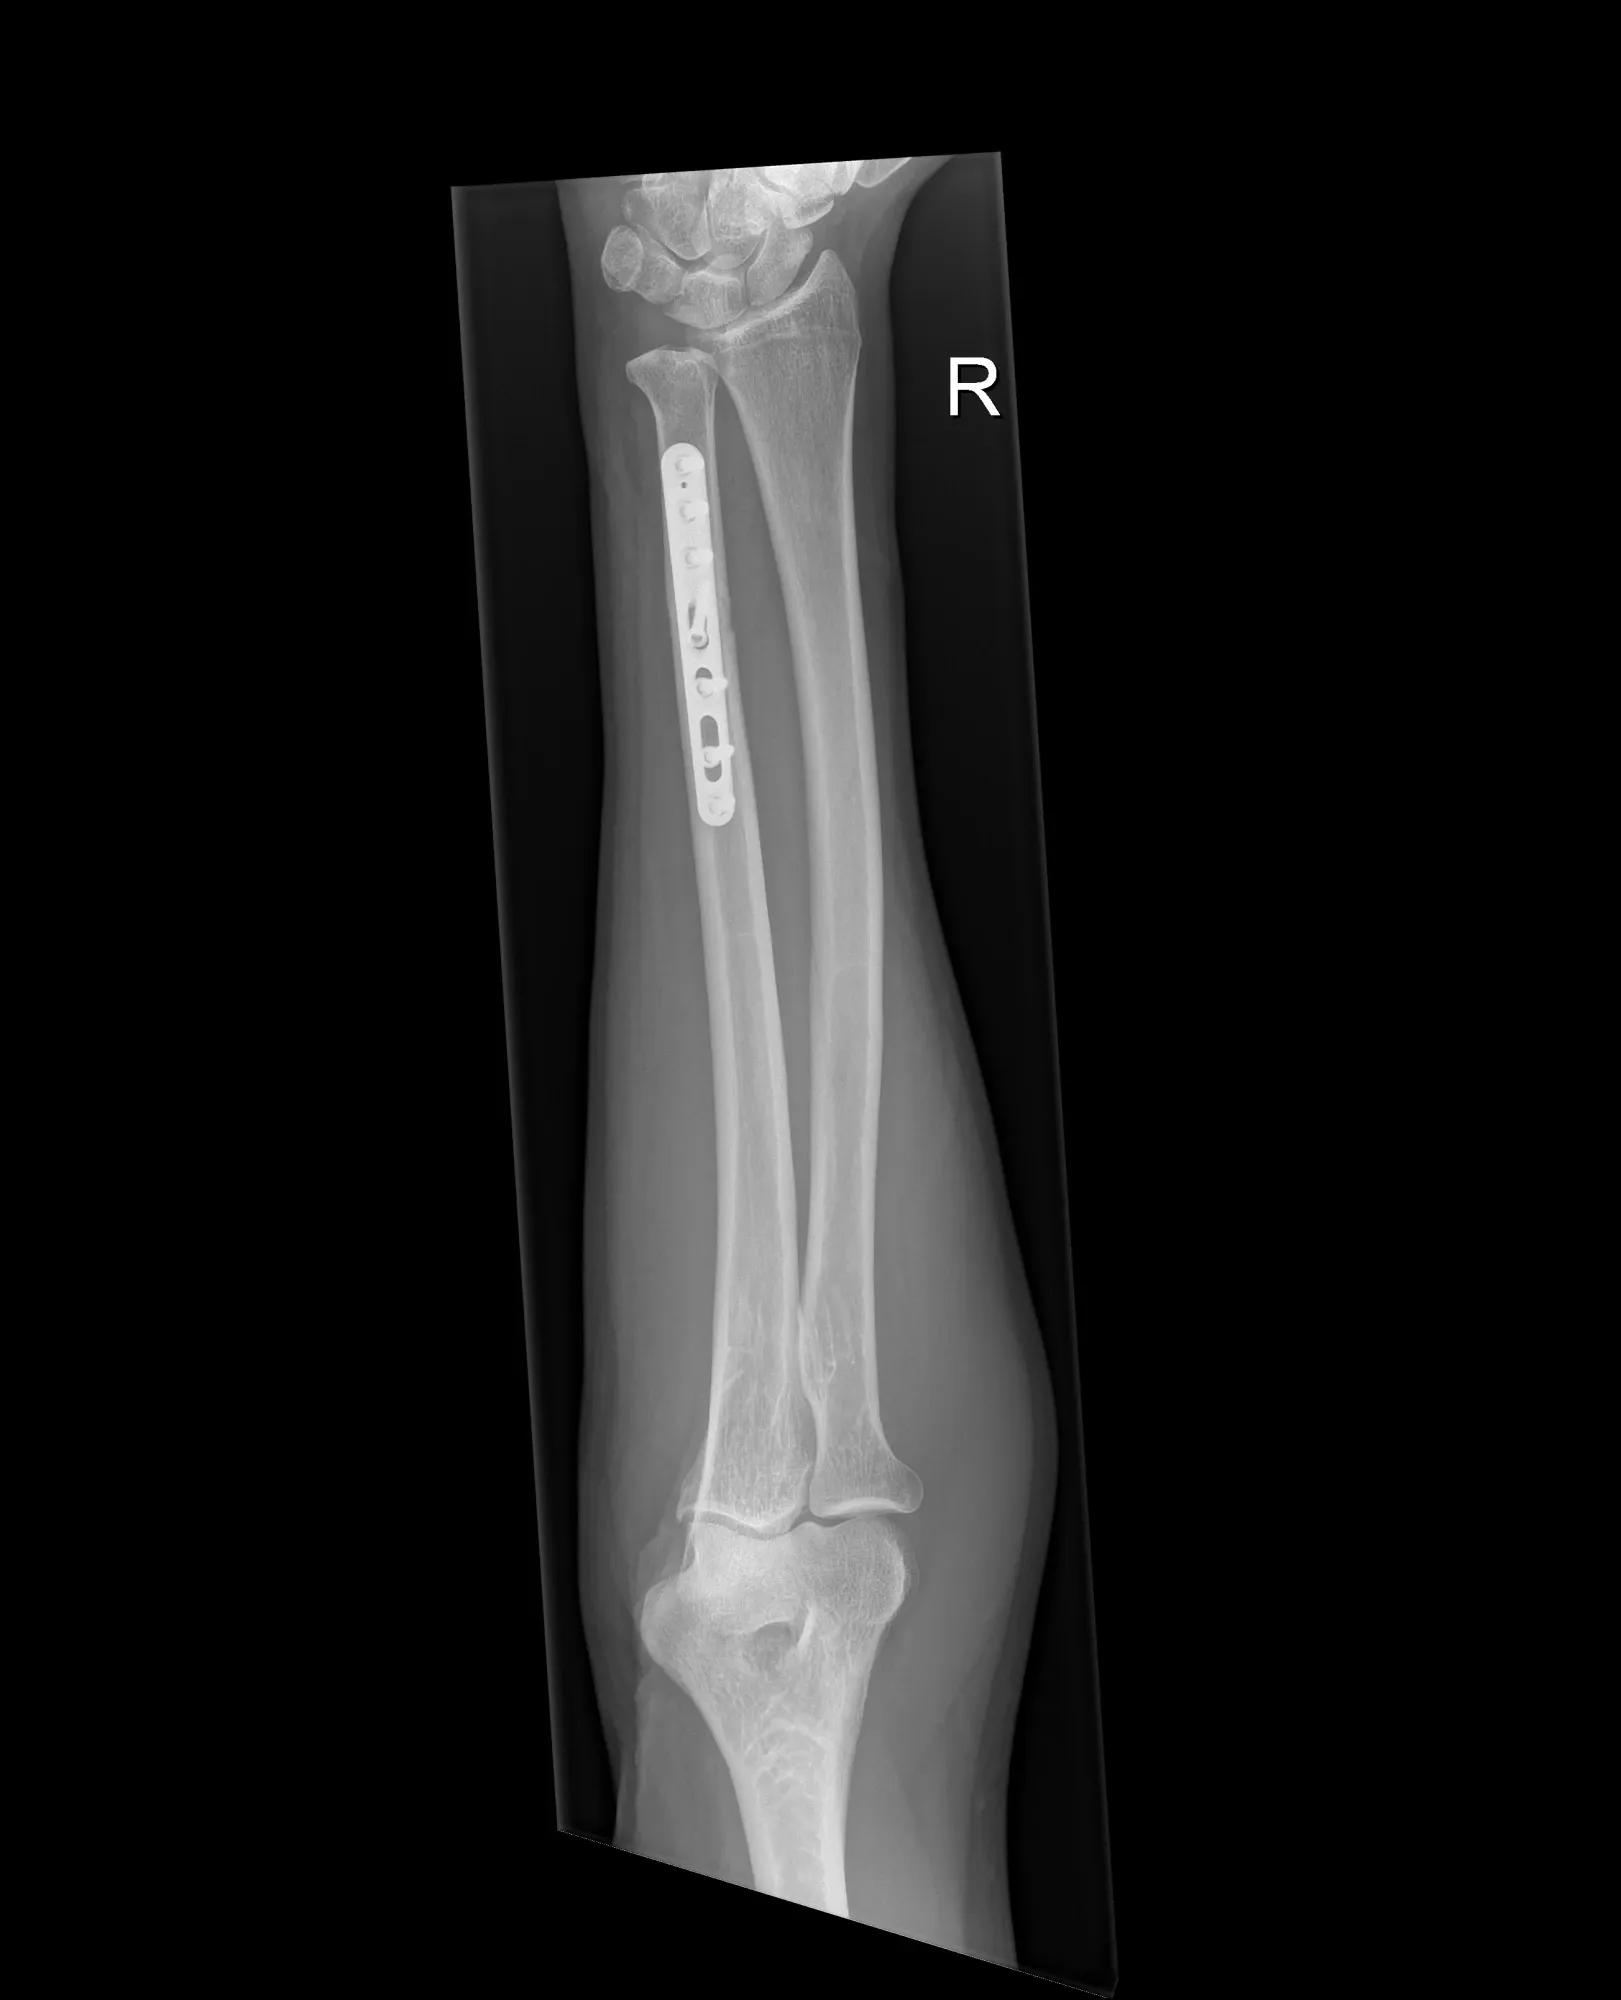

Chirurgisch:

Wanneer klachten blijven:

- Verkorting van de ulna

- De ellepijp wordt doorgezaagd, verkort en opnieuw vastgezet met een plaat en schroeven

- Bij kleine correcties kan de verkorting gebeuren via een polsartroscopie (kijkoperatie van de pols)

- In dagziekenhuis, meestal onder plexusverdoving